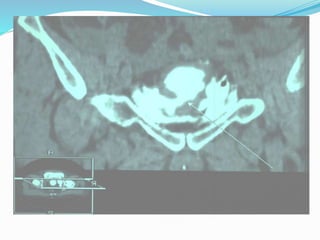

Injuries to the posterior urethra (PU) occur with pelvic

fractures, mostly as a result of motor vehicle accidents. The

male PU is injured in 4-19% of pelvic fractures, and the female

urethra in 0-6% of all pelvic fractures.

The combination of straddle fractures with diastasis of the

sacroiliac joint has the highest risk of urethral injury.

Injuries to theanterior urethra (AU) are caused by trauma during sexual intercourse (associated with penile fracture), penetrating trauma, placement of penile constriction bands, and from iatrogenic trauma e.g. endoscopic instruments, catheterisation. Injuries to the posterior urethra (PU) occur with pelvic fractures, mostly as a result of motor vehicle accidents. The male PU is injured in 4-19% of pelvic fractures, and the female urethra in 0-6% of all pelvic fractures. The combination of straddle fractures with diastasis of the sacroiliac joint has the highest risk of urethral injury. Injuries can vary from simple stretching to partial rupture to complete disruptions. Urethral injuries in women are rare.